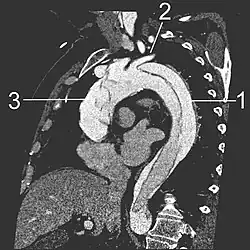

- Le scanner thoracique avec injection de produit de contraste dans le système vasculaire montre un double contraste de l'aorte qui est « coupée » en deux par le « flap ». Il permet de bien en délimiter l'extension. C'est l'examen à réaliser en première intention.

- L'échographie transœsophagienne consiste à faire avaler au patient, sous anesthésie locale, une sonde d'échographie fixé à un endoscope. L'examen permet de bien visualiser la quasi intégralité de l'aorte thoracique. En cas de dissection, le « flap » est clairement objectivé, ainsi que, parfois, la porte d'entrée et/ou de sortie. L'insuffisance de la valve aortique et son mécanisme peuvent être, également, facilement évalués. L'extension de la dissection vers l'aorte abdominale ne peut être analysée par cette technique, mais cette donnée reste secondaire dans la conduite à tenir (cf. classification des dissections).